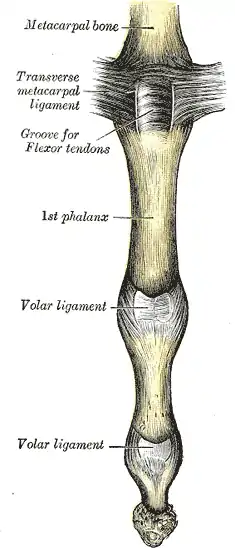

Palmar structures

In contrast, on the palmar side, a thick ligament prevents hyperextension. The distal part of the palmar ligament, called the palmar plate, is 2 to 3 millimetres (0.079 to 0.118 in) thick and has a fibrocartilaginous structure. The presence of chondroitin and keratan sulfate in the dorsal and palmar plates is important in resisting compression forces against the condyles of the proximal phalanx. Together these structures protect the tendons passing in front and behind the joint. These tendons can sustain traction forces thanks to their collagen fibers.[1]

Palmar ligament

The palmar ligament is thinner and more flexible in its central-proximal part. On both sides it is reinforced by the so-called check rein ligaments. The accessory collateral ligaments (ACL) originate at the proximal phalanx and are inserted distally at the base of the middle phalanx below the collateral ligaments.[1]

The accessory ligament and the proximal margin of the palmar plate are flexible and fold back upon themselves during flexion. The flexor tendon sheaths are firmly attached to the proximal and middle phalanges by annular pulleys A2 and A4, while the A3 pulley and the proximal fibres of the C1 ligament attach the sheaths to the mobile volar ligament at the PIP joint. During flexion this arrangement produces a space at the neck of the proximal phalanx which is filled by the folding palmar plate.[2]

The palmar plate is supported by a ligament on either side of the joint called the collateral ligaments, which prevent deviation of the joint from side to side. The ligaments can partially or fully tear and can avulse with a small fracture fragment when the finger is forced backwards into hyperextension. This is called a "palmar plate, or volar plate injury".[3]

The palmar plate forms a semi-rigid floor and the collateral ligaments the walls in a mobile box which moves together with the distal part of the joint and provides stability to the joint during its entire range of motion. Because the palmar plate adheres to the flexor digitorum superficialis near the distal attachment of the muscle, it also increases the moment of flexor action. In the PIP joint, extension is more limited because of the two so called check-rein ligaments, which attach the palmar plate to the proximal phalanx.[2]